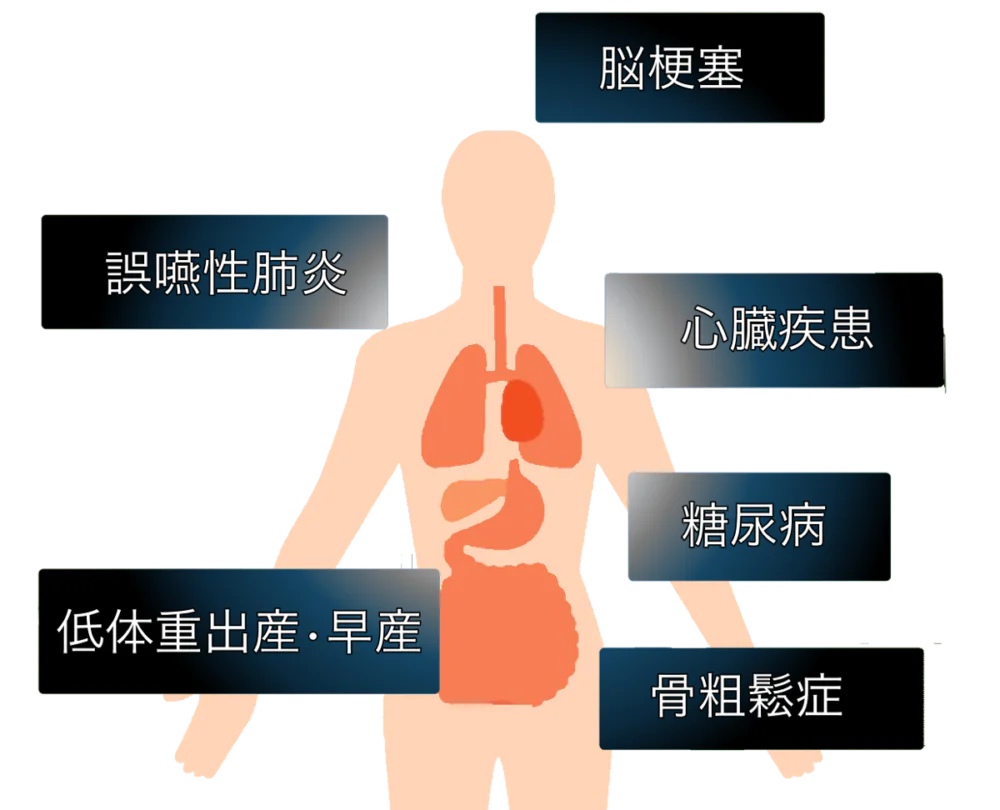

歯周病が全身に及ぼす影響

歯周病が進行すると、歯肉が炎症を起こし、その際に侵入した細菌や産生された有害物質が血液中に流れ込みます。これらの細菌や物質は血管内に侵入し、全身の各器官に広がります。歯周病は慢性疾患であり、歯周組織での炎症が持続的に細菌と有害物質の産生を引き起こし、それが継続的に全身に波及します。

この結果、歯周病は全身に対して様々な影響を及ぼす可能性があります。現在では、歯周病が血管系の病気(動脈硬化)、心臓疾患、脳梗塞、脳卒中、糖尿病や腎臓病、関節リュウマチ、呼吸器疾患、早期低体重児の出産などに関連していると考えられています。